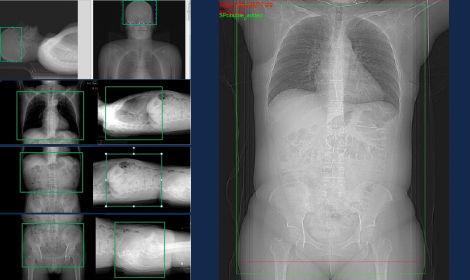

Automatische Positionierung

Die KI-basierte automatische Positionierung optimiert den Workflow der Patientenpositionierung, indem viele Einzelschritte auf einen einzigen Klick reduziert werden. Sie erfasst zunächst Referenzpunkte und zeigt den Scout-Scan-Bereich auf dem Xtream-Tablet an. Anschließend werden die korrekte Tischhöhe und die Tischbewegungen bestimmt, um die Mitte des Scan-Bereichs am CT-Isozentrum auszurichten.

Automatische Referenzpunkte und Scout-Bereich-Anzeige

• Erkennt Referenzpunkte mithilfe eines Deep-Learning-Algorithmus und zeigt den Scout-Scan-Bereich auf dem Xtream-Tablet an

• Ermöglicht die visuelle Bestätigung und interaktive Anpassung des Scan-Bereichs auf dem Touchscreen

GEHCEffortlessWorkflowPre-scanImage3

Automatische Zentrierung

• Legt die Mitte des Scout-Scan-Bereichs fest und richtet sie am CT-Isozentrum aus

• Reduziert die Notwendigkeit von Neupositionierungen und einer Scanwiederholung aufgrund der höheren Genauigkeit

GEHCEffortlessWorkflowPre-scanImage4

Automatische Patientenpositionierung

• Bewegt den Patienten mit integrierter KI automatisch zur Startposition des Scans

• Optimiert den Workflow durch Reduzierung des Positionierungsprozesses auf einen einzigen Klick